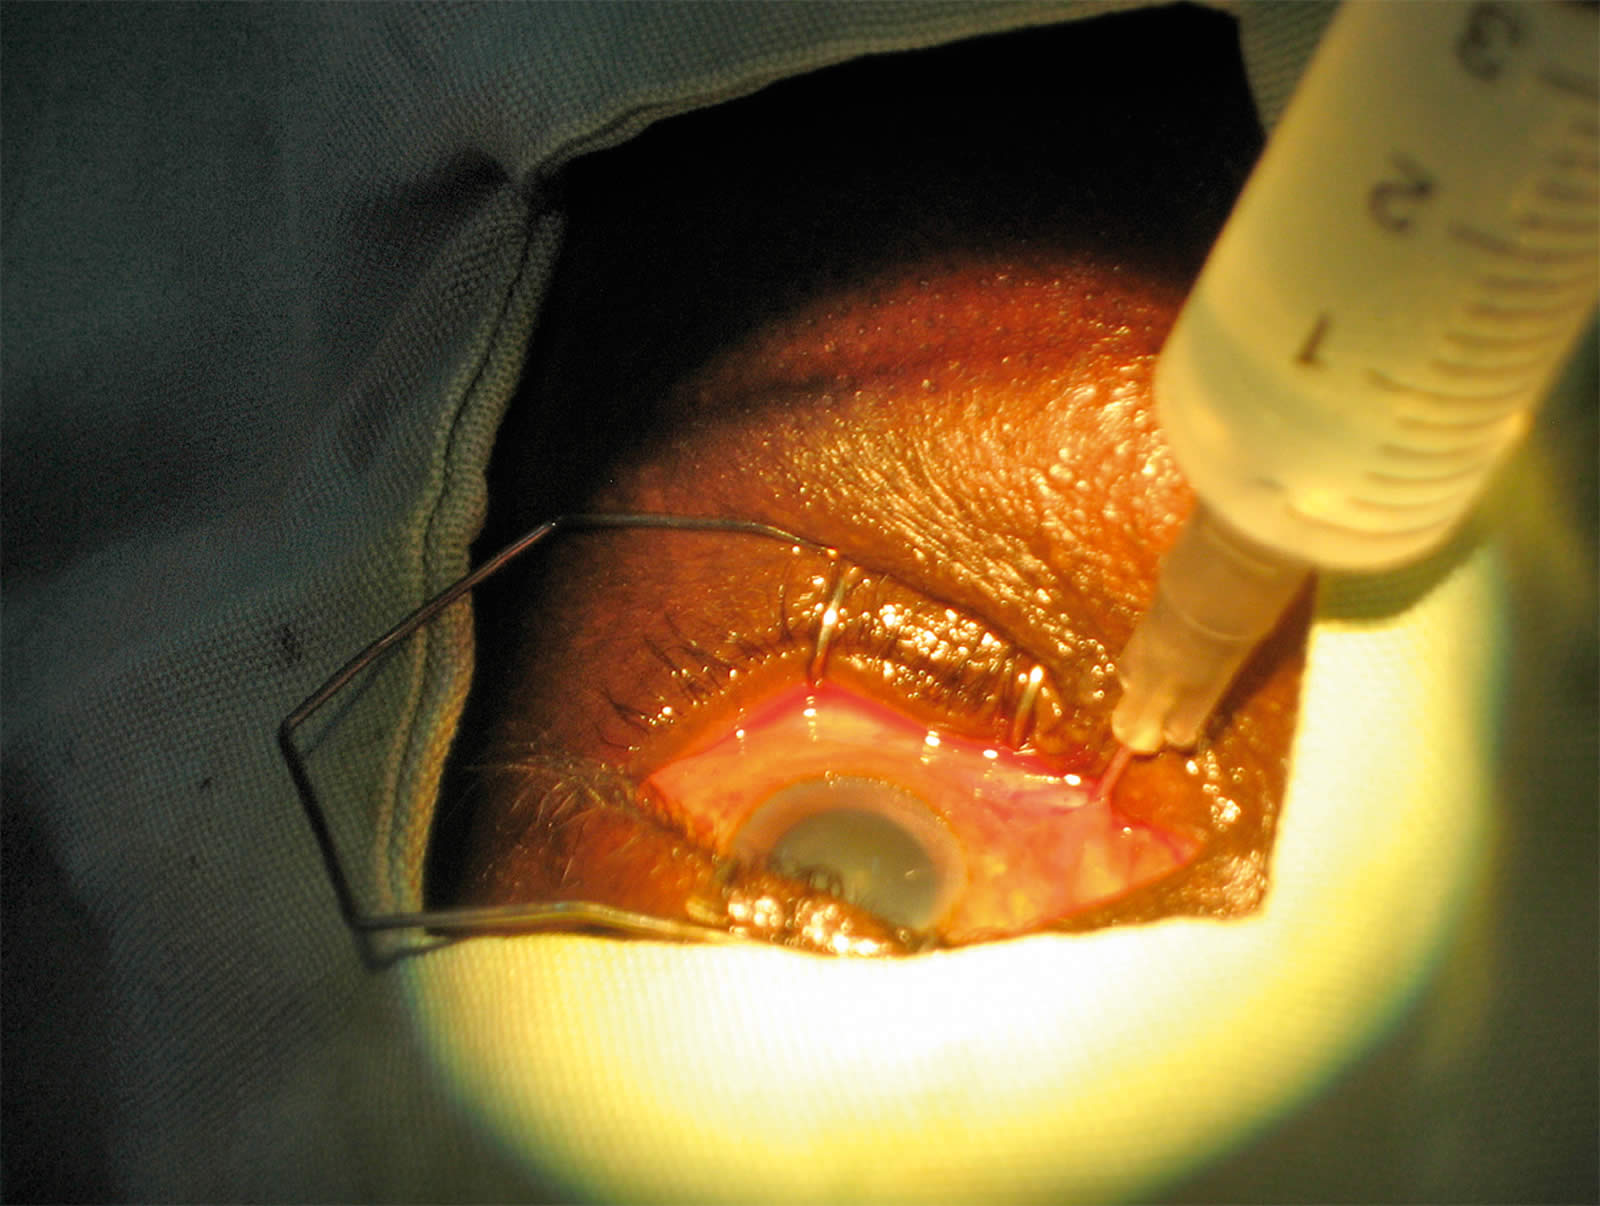

- Use a pair of spring scissors to make a small (0.5 mm long) snip through both the conjunctiva and Tenon’s capsule, 2 to 3 mm behind the limbus in the inferomedial quadrant of the globe. The scissors should not be opened more than halfway. It is essential to find the sub-Tenon’s plane, i.e. to dissect down to bare sclera. It helps to hold the scissor blades so that their plane is perpendicular to the ocular surface instead of being parallel to it (Figure 5).

- Use a specially designed blunt cannula to inject the anaesthetic. However, if you do not have a specially designed cannula, a lacrimal cannula is a suitable alternative. Mount the cannula on a syringe containing the anaesthetic solution.

- Pass the cannula through the snip incision. The incision should fit tightly around the cannula.

- Advance the cannula backwards with its tip touching and following the curvature of the globe all the way to the retrobulbar space. As the equator is passed, the hand and syringe need to rotate away from the globe so that the cannula tip stays in the space (Figure 6). Inject the anaesthetic carefully.